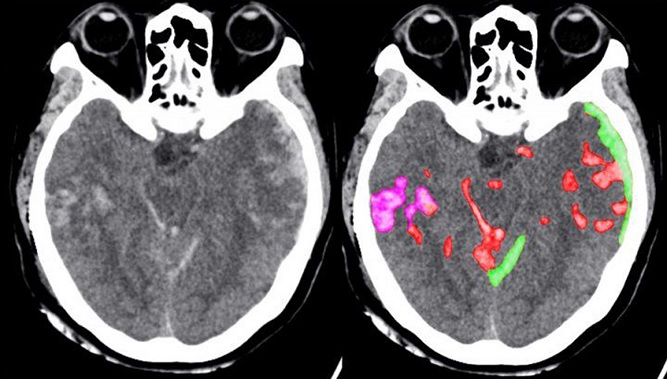

یکی از مواردی که به تازگی دانشمندان در آن رو به استفاده از هوش مصنوعی آوردهاند در زمینه شناسایی خونریزی مغزی و تشخیص سریع بیماران در حین تصادفات است.

در این حالت هنگامی که تصویر CT Scan مغزی فرد به الگوریتم داده میشود با توجه به شناسایی نقاط آسیب دیده در سطح پیکسل، سعی میشود تا احتمال وقوع خونریزی مغزی را مورد کاوش قرار داده و در صورتی که به سطحی از اطمینان رسیدیم، اعلام خونریزی در آن ناحیه مغزی صورت میگیرد.